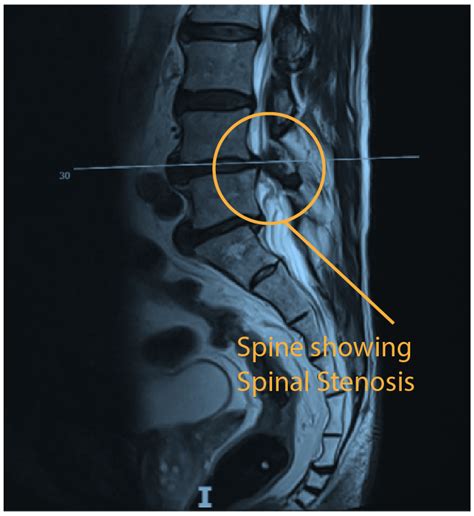

Evaluating Effective Medication Options For Spinal Stenosis Relief

What is Spinal Stenosis? - Orthopaedic Medical Group of Tampa Bay